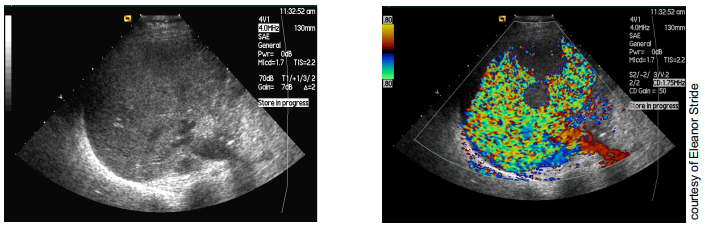

what is loss of correlation imaging

colour doppler mode is used to produce high pressure waves popping the contrast agent

released gas produces strong reflections

doppler interprets this as large random velocity fluctuations

used for perfusion studies → areas without bubbles → not perfused

very sensitive but low frame rate